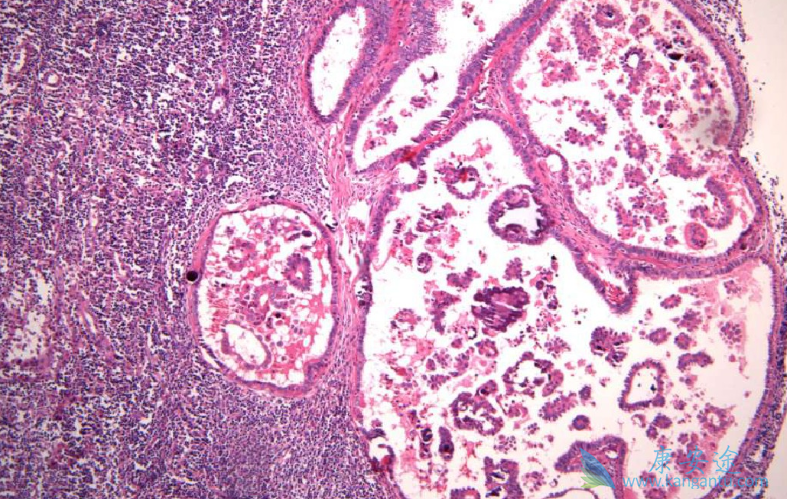

肿瘤发生的过程是长期的、复杂的,肿瘤的发生需要两个条件一起的作用才能够形成:时间和空间,它需要几十年、多个阶段才能完成,并不是有基因突变就有肿瘤。很多肿瘤发生前会有一个良性肿瘤的阶段,比如结肠肿瘤发生之前的管状腺瘤,宫颈肿瘤发生之前的宫颈上皮内瘤变。